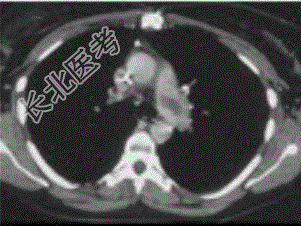

- 单项选择题患者女,51岁, 心脏手术后,突感胸痛, 结合CT图像,最可能的诊断是

A、肺栓塞

B、支气管扩张

C、肺水肿

D、肺癌

E、肺不张